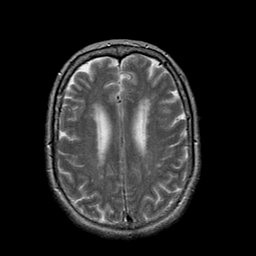

Stroke:T2-weighted MR #1 -- Slice #17

[Home][Help][Clinical] Slice 17